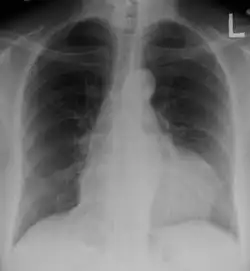

Manifestaciones pulmonares

En el LES se puede observar pleuritis, con o sin derrame pleural, neumonitis intersticial, hipertensión pulmonar y hemorragia alveolar. Además, el riesgo de acontecimientos tromboembólicos está aumentado en los pacientes con anticuerpos antifosfolípidos.[60]

La tos se asocia la mayoría de las veces, con infección respiratoria alta de etiología vírica; sin embargo, la afectación pulmonar en el lupus debe ser objeto de evaluación cuidadosa, para descartar neumonitis lúpica aguda, caracterizada por pleuresía, disnea, tos y fiebre, con infiltrados pulmonares en las radiografías, que precisa tratamiento inmunosupresor y cuidados respiratorios de soporte.[19]

La presencia de disnea, dolor torácico pleurítico episódico y disminución progresiva del volumen pulmonar en ausencia de fibrosis intersticial o enfermedad significativa de la pleura sugiere la presencia del síndrome del pulmón encogido.[19]